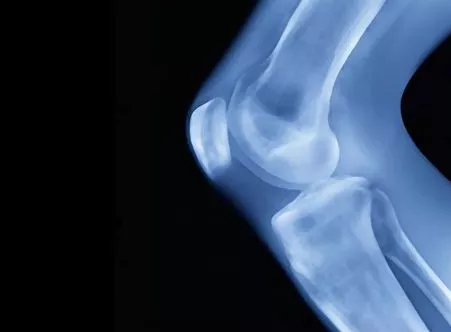

Исследование пористости костных и тканевых структур на основе данных микро-КТ/МРТ Исследование пористости костных и тканевых структур на основе данных микро-КТ/МРТ

Проводите анализ структуры и плотности костей пациента на основе снимков микротомографии для разработки имплантатов с быстрой приживаемостью в ткани и надежной фиксацией.

Модули для решения задачи:  Mimics Base / FEA

Преимущества:  Анатомический анализ: количественная оценка анатомических структур для разработки дизайна имплантата и наиболее эффективной стратегии лечения / Создание экспериментальных моделей для проверки конструкции имплантата, планирования лечения и обучения врачей-стажеров / Компьютерное моделирование: имплантация протеза на трехмерной модели для оптимального подбора имплантата с учетом всех анатомических особенностей пациента

Примеры внедрения:  Оптимизация предоперационного планирования / Проектирование индивидуального черепного имплантата / Конечно-элементное моделирование тазобедренного сустава / Индивидуальные анатомические модели для лечения аневризмы